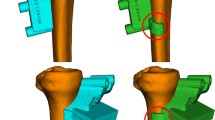

Moderate-to-large alignment changes after medial opening-wedge HTO resulted in a significant shift in intraarticular contact pressures from the medial compartment of the knee towards the lateral compartment (pressure ratio: 1.9; P < 0.05). However, fixation of the distal tibial segment at 15° of external rotation neutralized this intended beneficial effect (pressure ratio: 1.1; P < 0.05) (Figs. 1a, b, 2). A significant increase in tibiofemoral contact area was also observed in the medial compartment (P < 0.05) (Fig. 3a, b).

Visualization of the changes in intraarticular knee pressures in a single specimen as a function of alignment correction and distal tibial rotation. Alignment correction successfully shifted the load towards the lateral compartment. On the other hand, malrotation of the distal tibial segment led to increased pressures in the medial compartment